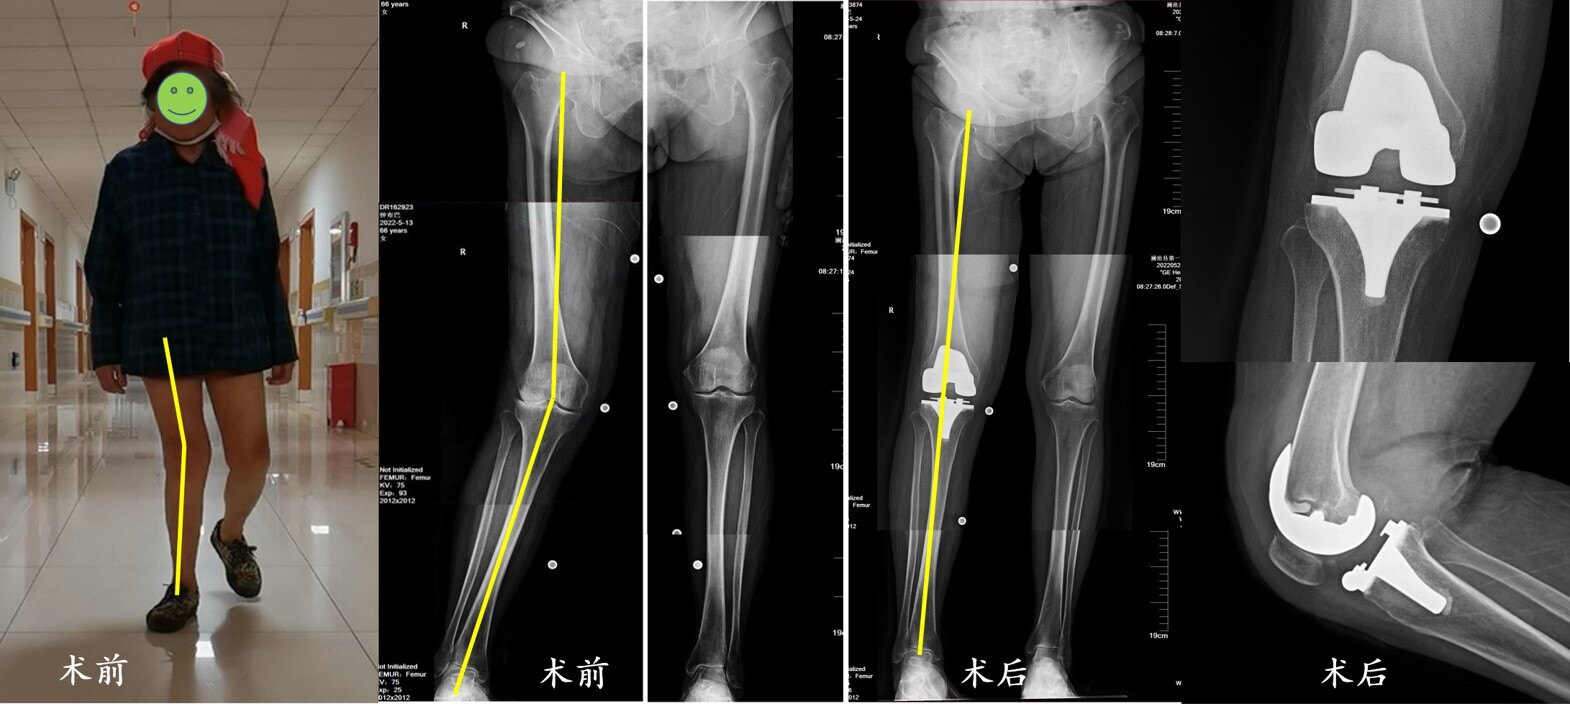

病例4(图7):61岁的李女士双膝关节反复肿痛7年多,平时的行走活动受到严重影响,甚至难以操持一些简单的家务,遂来到澜沧县第一人民医院骨科就诊,X线检查发现膝关节已经明显的磨损、变形,于是骨科团队的帮助下先选择了左侧人工膝关节置换手术,解除了关节病痛,下肢的内翻畸形也得到了矫正。手术后第1天就开始了下床活动进行恢复锻炼,第6天出院回家继续康复。

图7. 李女士因左膝严重骨关节炎接受了人工膝关节置换手术。